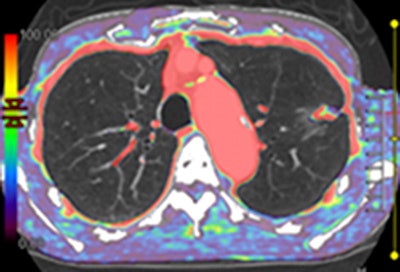

| Axial images of primary lung cancer (adenocarcinoma) in left upper lung lobe in 76-year-old man. Above, thin-section CT image shows nodule 18 mm in diameter in left upper lobe. Below, perfusion map shows nodule has high perfusion, with PFMS (scale at left) determined to be 89.9 mL/100 mL/min; this is a true-positive case according to maximal slope method results. Bottom, integrated PET/CT image shows high uptake of FDG, with SUVmax of lesion determined to be 3.8, indicating a true-positive case. Images republished with permission of the Radiological Society of North America from Radiology, February 2011, Vol. 258:2, pp. 599-609. |